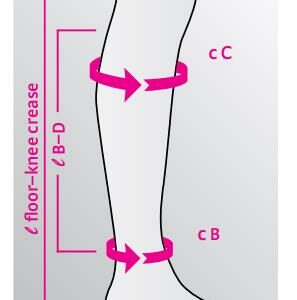

Kokotaulukko

S = cB < 36 cm cA1 19-24 cm

M = cB < 36 cm cA1 24-29 cm

L = cB < 41 cm cA1 29-34 cm